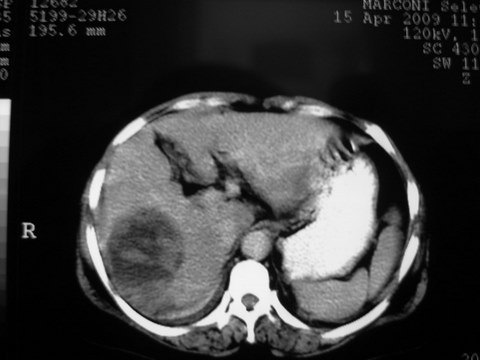

患者 女 51岁 两天前感觉上腹疼,无明显诱因,b超示肝右叶囊实性占位,边缘清楚,其内回声不均匀,ct增强如图,大家看看是什么 ,病人一年前及两月前b超检查只是提示胆囊炎

外院术后,证实肝癌合并出血

特点:1,病灶发展迅速,(2月前正常)[br] 2,囊实性,且并边界清晰光滑,呈右后叶赘生性。囊性区无强化,实性部分较多轻度强化,边界欠清。考虑囊腺癌或囊腺瘤。

出病理 中分化肝细胞癌合并出血